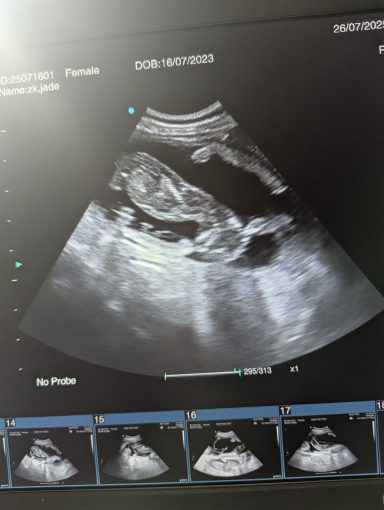

Ultrasound pregnancy scanning is a safe, non-invasive way to confirm pregnancy in dogs and cats, offering breeders and pet owners peace of mind and vital information to support responsible care. It allows us to detect gestational sacs, assess foetal development, and estimate litter size—all while ensuring the wellbeing of the animal.

Pregnancy can sometimes be detected as early as Day 18 post-mating, but scanning at this stage is not routinely recommended. Embryos are still developing and may not be clearly visible, and there is a natural risk of embryo resorption, which can lead to misleading or inconclusive results.

For the most accurate and reliable scan, we advise booking between Day 25 and Day 32, when pregnancy is more easily confirmed and foetal structures are clearer. If an early scan is performed and no pregnancy is detected, we offer a FREE complimentary re-scan after 7 days at the clinic to ensure clarity and support informed decision-making.

Our approach balances early insight with ethical care—always prioritizing the comfort of the animal and the accuracy of the results.

Gallery